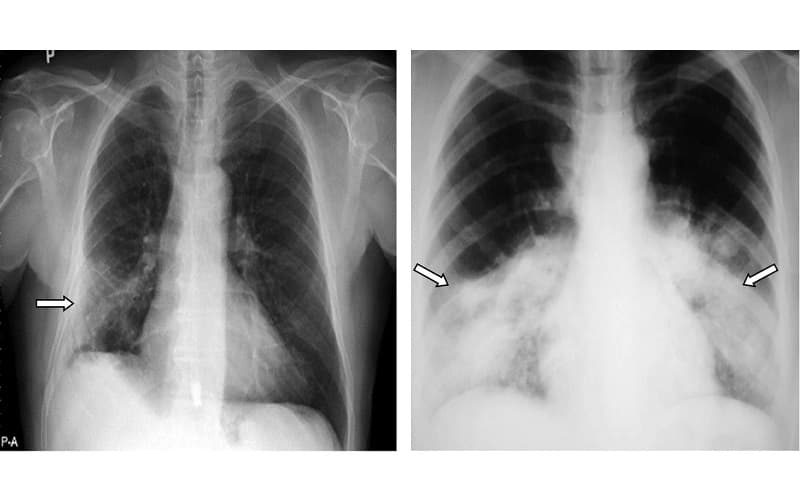

3.1. Chụp X quang ngực

Chụp X quang là bước đầu tiên trong quy trình chẩn đoán. Hình ảnh X quang có thể cho thấy các tổn thương mô kẽ như dày mô kẽ, lưới mờ, hình ảnh tổ ong… Tuy nhiên, X quang có thể bỏ sót các tổn thương nhỏ, nên thường cần kết hợp với các phương pháp khác.

Chụp X quang là một trong những phương pháp chẩn đoán quan trọng cho viêm phổi kẽ